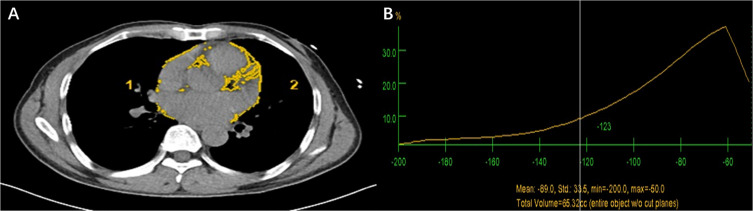

Methods: Patients diagnosed with STEMI were continuously included, all patients underwent PCI within 12 hours of onset. EAT volume was measured and obtained by chest CT. Logistic regression analysis was used to analyze possible risk factors for CI-AKI. Restricted cubic splines (RCS) were utilized to explore the dose-response relationship involving EAT and CI-AKI.